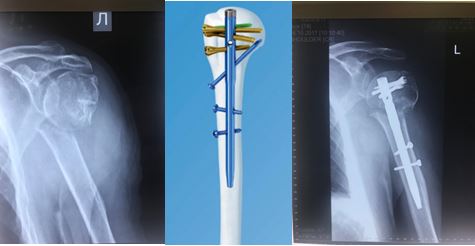

Переломы плечевой кости

Подразделяются на переломы проксимального и дистального эпифизов (концевых участков кости), а также диафиза (центрального отдела плечевой кости, между двумя эпифизами).

Несколько лет назад при переломах проксимального отдела плечевой кости, так называемой хирургической шейки плеча, использовался метод накостного остеосинтеза – пластина с анатомическим дизайном. Данная операция производится из обширного хирургического доступа, что в послеоперационном периоде требует дополнительного внимания и бережного отношения к ранней реабилитации.

В настоящее время специалисты ЦТиО ГВКГ им. Н.Н. Бурденко выполняют остеосинтез подобных переломов по минимально-инвазивной методике через небольшие проколы, без нарушения целостности капсулы сустава и мышц. Это позволяет достичь функционального результата в более сокращенные сроки.

Переломы области диафиза плечевой кости также оперируются по минимально-инвазивной методике с применением интрамедуллярного штифта с блокированием. Различают антеградный (через проксимальный отдел плечевой кости) и ретроградный (через дистальный отдел плечевой кости) остеосинтез. Метод выбора зависит от линии перелома.